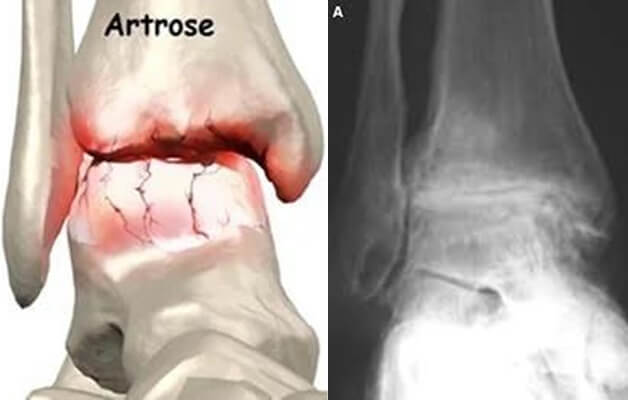

O diagnóstico por imagem é baseado em radiografias em carga, em que se visualiza o estreitamento do espaço articular, esclerose do osso subcondral, formação de osteófitos e possíveis deformidades articulares. A artrose do tornozelo pode passar despercebida nos estadios iniciais com as radiografias, podendo nestes casos ser necessário o estudo complementar com tomografia computorizada ou ressonância magnética.